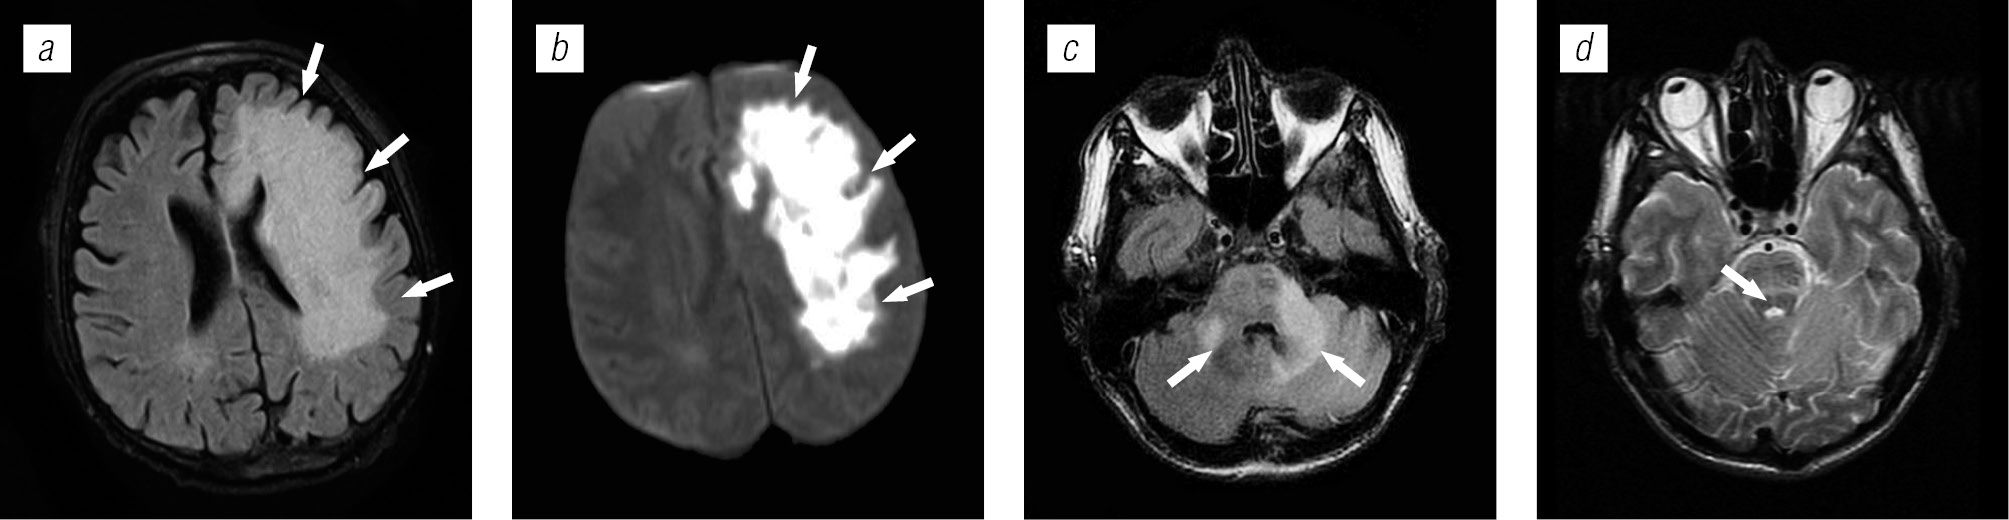

Структура оппортунистических и вторичных заболеваний была представлена токсоплазмозом головного мозга (18,3 %), герпесвирусными поражениями (12,2 %), прогрессирующей мультифокальной лейкоэнцефалопатией (10,24 %), нейроинфекцией неуточненной этиологии (12,2 %), криптококкозом (4,39 %), туберкулезом (2,44 %), лимфомой головного мозга (2,44 %), МАК-инфекцией (0,24 %).